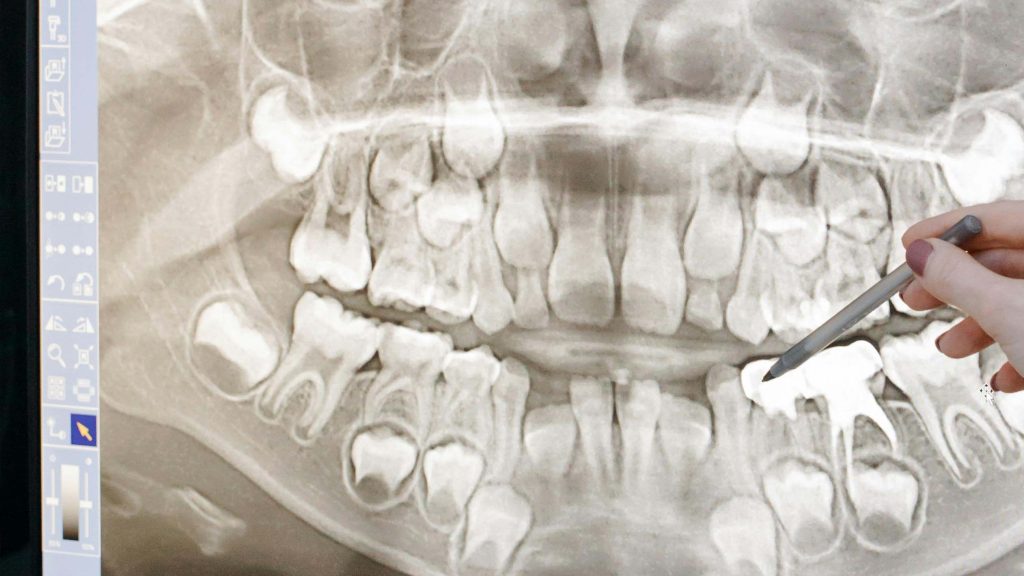

Verstandskiezen zijn de kiezen helemaal achterin je mond. De meeste mensen krijgen er vier: twee boven en twee onder. Ze komen meestal door als je tussen de 17 en 25 jaar bent. Niet iedereen krijgt ze, en soms groeien ze zonder problemen. Maar vaak is er niet genoeg ruimte in je kaak, en dan kunnen er klachten ontstaan.

Bij veel mensen groeien verstandskiezen scheef of komen ze maar half door. Dit kan zorgen voor: pijn achter in je mond, ontstoken tandvlees, moeite met eten, stinkende adem, en gaatjes omdat het moeilijk schoon te houden. In hele zeldzame gevallen zou je zelfs een tumor kunnen krijgen. Aldus de kliniek voor tandheelkunde.

Soms is het verwijderen wat moeilijker omdat de kies niet meer recht staat, tijdens het trekken zelf merk je daar niet heel veel van maar dat kan er wel voor zorgen dat je achteraf iets meer pijn krijgt en dat je kaak een beetje opzwelt.